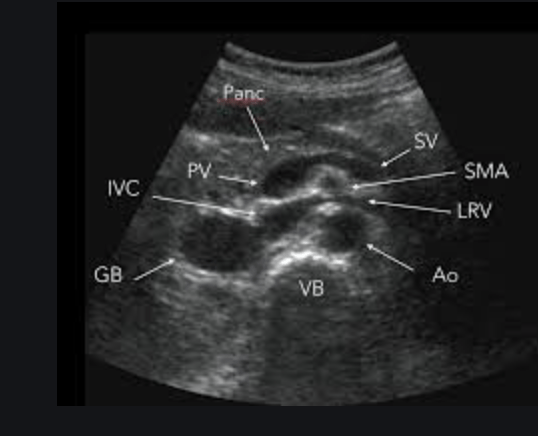

Aortic Ultrasound

Identify the aorta based on anatomy, not on pulsatility or color flow (there are times where the IVC can appear to be pulsatile and may lead to misidentification). The aorta should appear as a “sad cookie monster” with the IVC and aorta making up the eyes, and the vertebral body making up the frown. You can identify the vertebral body as a hyperechoic “frown” with anechoic shadow behind it.

You should attempt to locate the major branches when ultrasounding to aid in proper identification and to ensure you are scanning the entire aorta. Obtain views of the celiac, SMA, and aortic bifurcation.

The SMA can be identified from the “matador sign.” The SMA, PV, and SV form a matador hat like shape.

Measure the aorta anterior the posterior, outside wall to outside wall. We want to overestimate the size in order to be as sensitive as possible. Fusiform aneurysms that would only show up with lateral wall to lateral wall measurements are very rare. Also, the lateral walls on ultrasound will be less accurate due to the direction of the beam and artifact than the anterior and posterior walls. Normal aortic measurement should be less than 3cm, with the risk of rupture greatly increasing over 5.5cm.